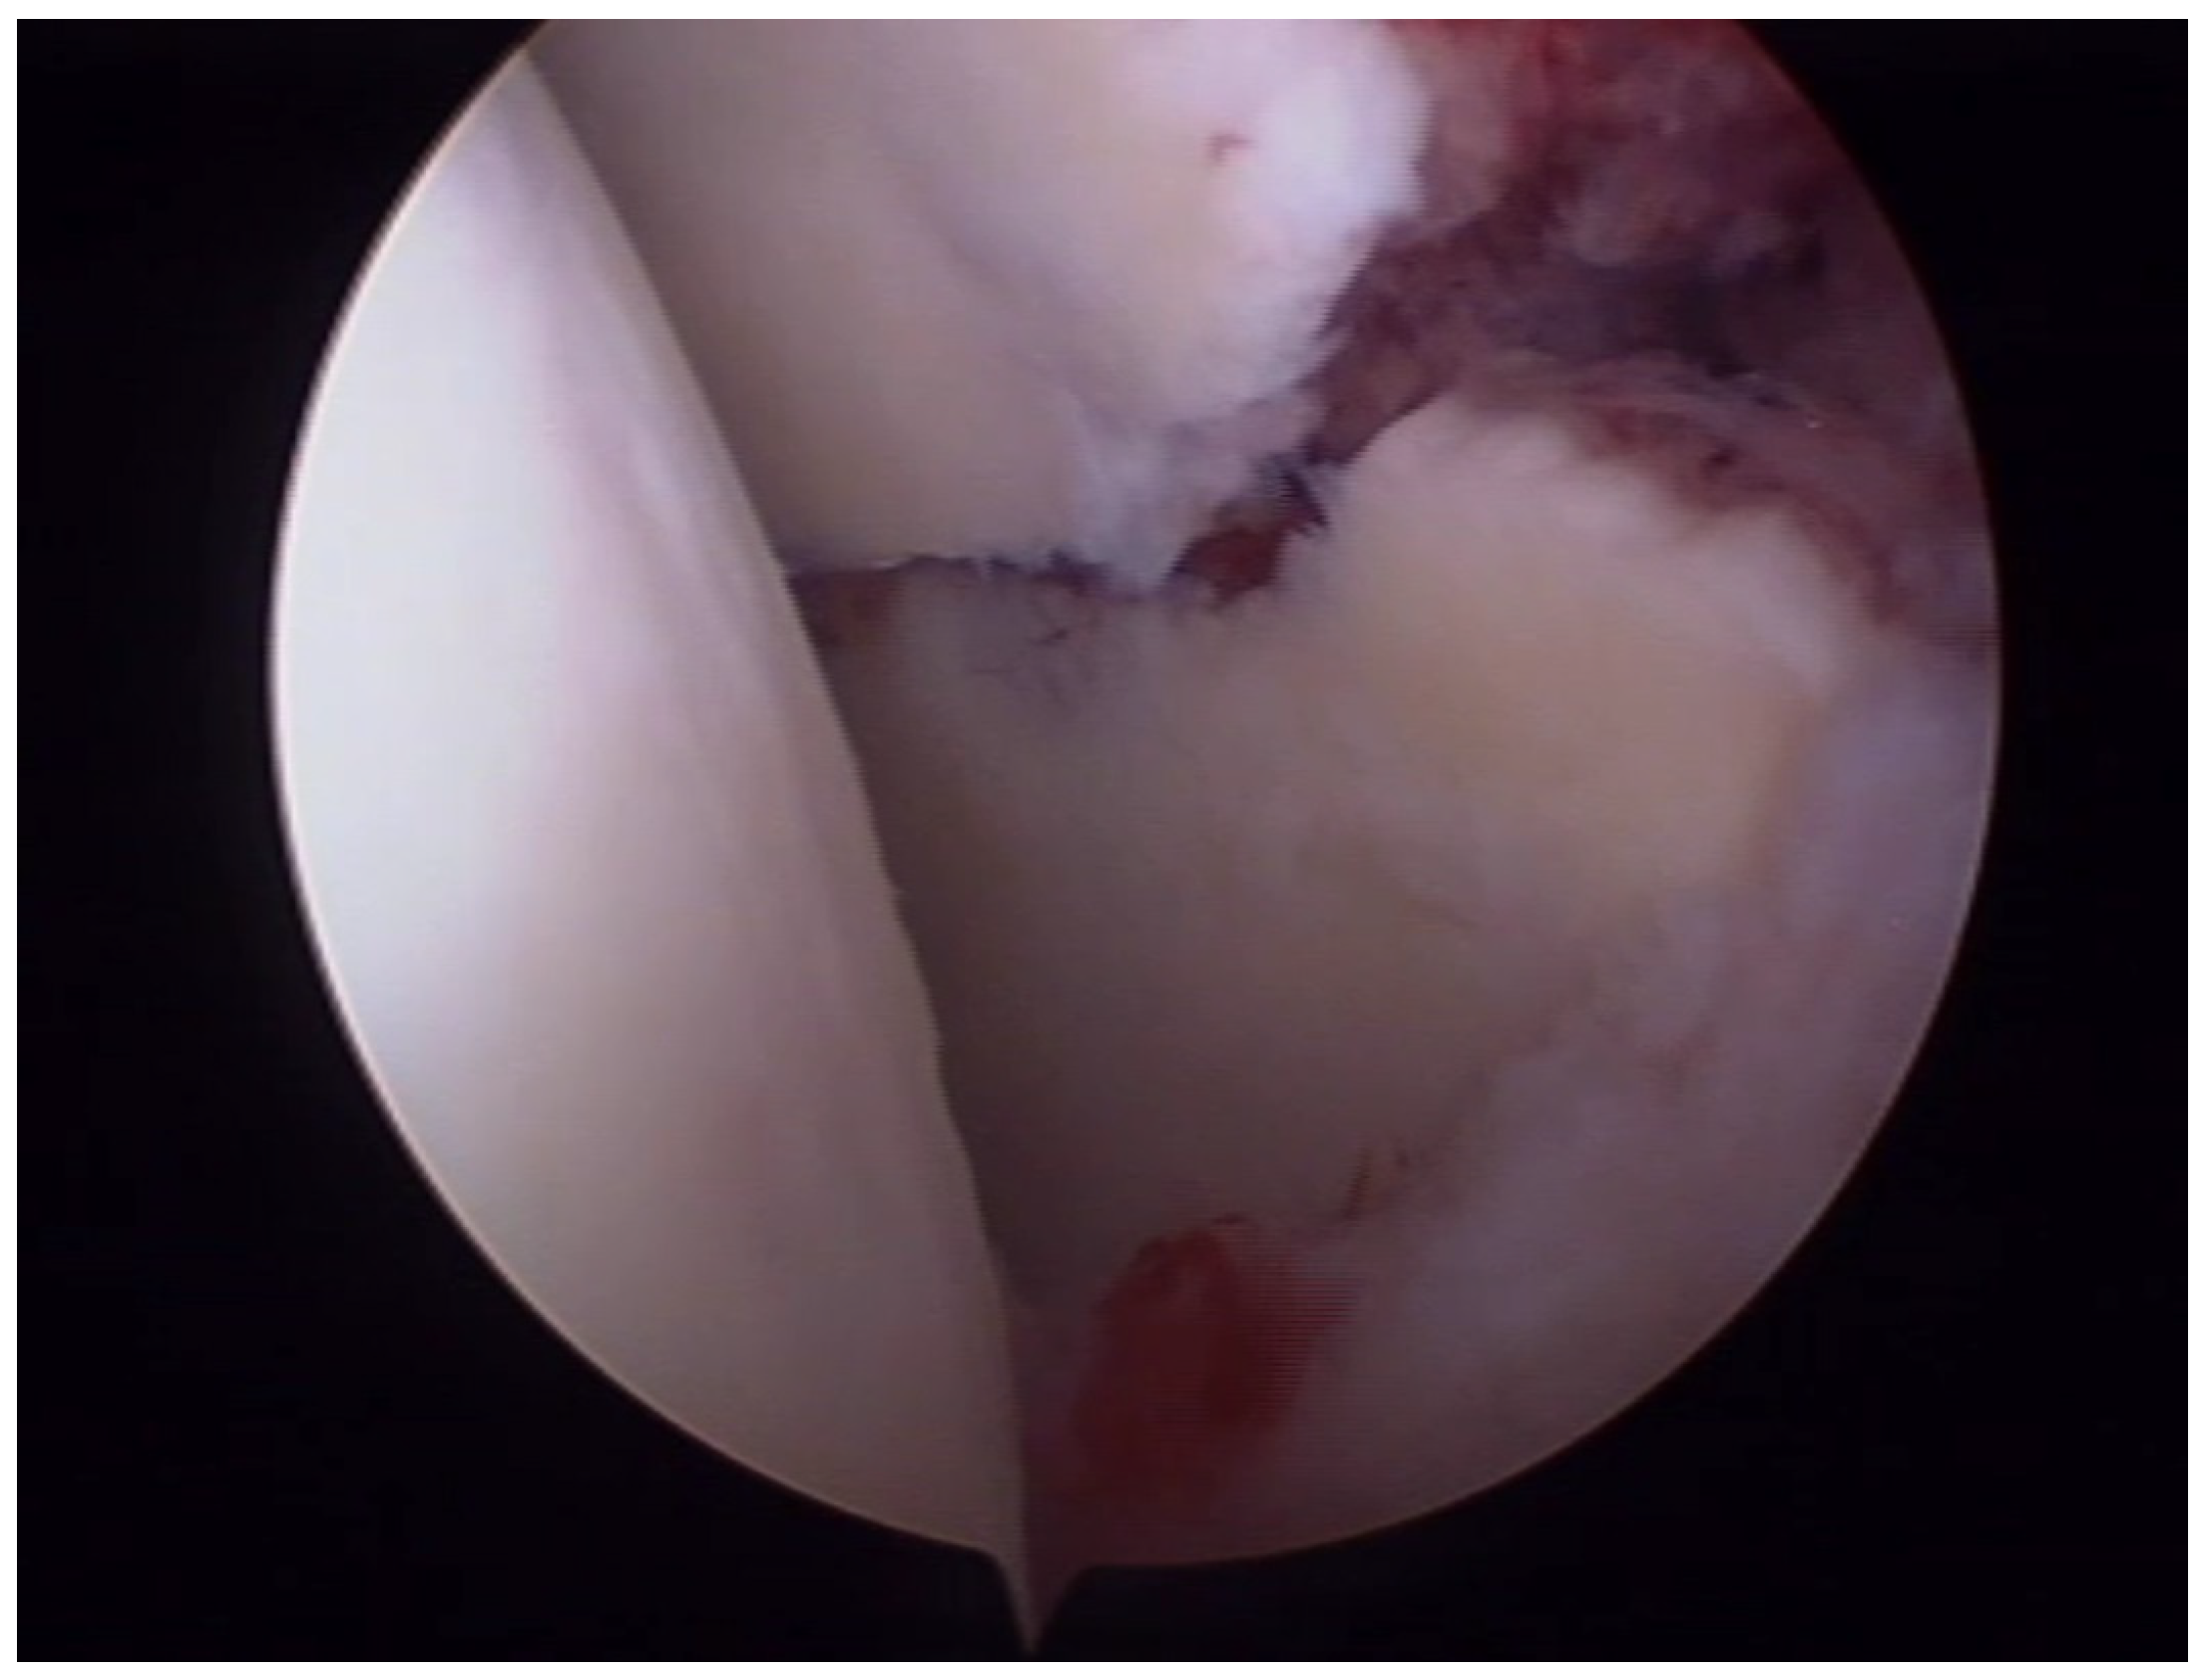

6.1. Ideberg Type III Fractures

- Tao, M.A.; Garrigues, G.E. Arthroscopic-Assisted Fixation of Ideberg Type III Glenoid Fractures. Arthrosc. Tech. 2015, 4, e119–e125. [Google Scholar] [CrossRef] [PubMed]

- Acharya, P.; Arora, B.; Pinto, N. Arthroscopy Assisted Percutaneous Fixation of Ideberg Type Iii Glenoid Fractures. J. Orthop. Case Rep. 2015, 5, 41–43. [Google Scholar] [CrossRef]

- Yang, H.B.; Wang, D.; He, X.J. Arthroscopic-assisted reduction and percutaneous cannulated screw fixation for Ideberg type III glenoid fractures: A minimum 2-year follow-up of 18 cases. Am. J. Sports Med. 2011, 39, 1923–1928. [Google Scholar] [CrossRef] [PubMed]

- Bonczek, S.J.; Hutchinson, R.; Chakravarthy, J. An innovative method of fracture reduction in an arthroscopically assisted cannulated screw fixation of an Ideberg type III glenoid fracture. Int. J. Shoulder Surg. 2015, 9, 56–59. [Google Scholar] [CrossRef]